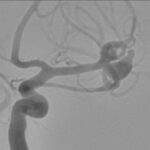

Fig. 3. Angiografia digital 3D: Aneurisma sacular pequeño bilobulado, con pseudoaneurisma asociado, responsable del sangrado.

Fig. 5. Angiografia digital con substracción: Aneurisma sacular pequeño bilobulado, con pseudoaneurisma asociado, responsable del sangrado, a nivel de la bifurcación de la arteria cerebral media izquierda.